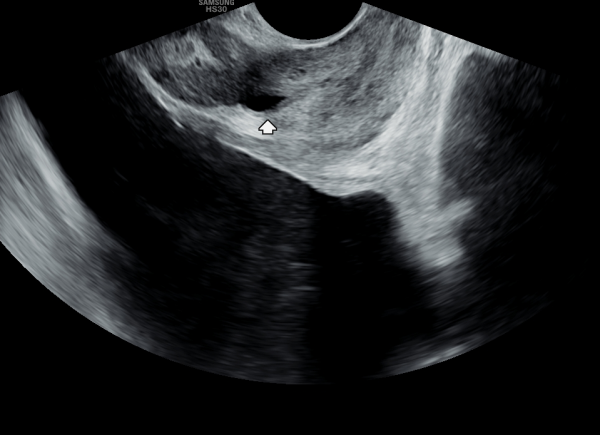

첫 내원 당일 경직장 전립선 초음파 검사상 사정관의 순환 장애로 정낭의 다발성 낭종이 관찰되는 사진입니다.

This is a transrectal prostate ultrasound image taken on the first day of the patient’s visit, showing multiple seminal vesicle cysts caused by impaired circulation in the ejaculatory ducts.

주 2~3회 전립선의 표적 치료후 전립선과 사정관과 정낭 그리고 정관의 순환 장애가 개선되어 정낭의 다발성 낭종이 좋아지고 있는 경직장 정낭의 초음파 사진입니다.

A transrectal ultrasound image of the seminal vesicles showing improvement of multiple seminal vesicle cysts as a result of enhanced circulation in the prostate, ejaculatory ducts, seminal vesicles, and vas deferens following targeted prostate therapy administered 2 to 3 times per week.